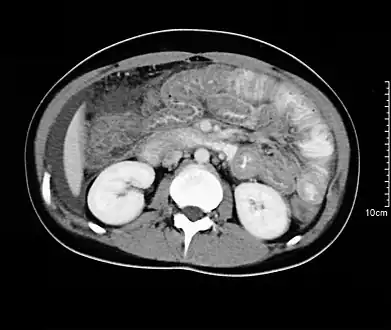

Hypereosinophilia, the hallmark of allergic response, may be absent in up to 20% of patients, but hypoalbuminaemia and other abnormalities suggestive of malabsorption may be present. CT scans may show nodular and irregular thickening of the folds in the distal stomach and proximal small bowel, but these findings can also be present in other conditions like Crohn's disease and lymphoma.

Spiral CT showing ascites and concentric thickening of colon and ileum in EG